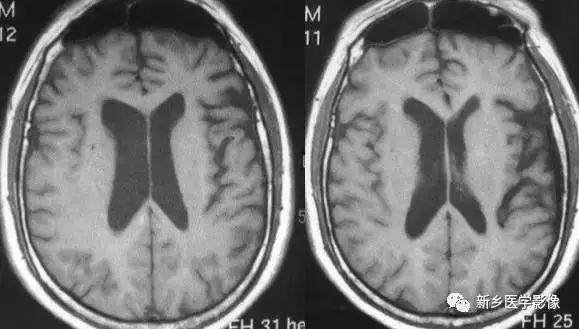

普遍性脑萎缩常同时累及灰质和白质.可表现有双侧侧脑室扩大。而且是双侧侧脑室轻度对称性扩大最常见的原因。尤其是以脑白质萎缩为主的病人。

普遍性脑萎缩引起的侧脑室扩大通常比较对称.中线无移位。其特点是同时有脑沟、脑裂增宽等脑皮质萎缩的表现.

普遍性脑萎缩可见于正常老年人

原因有:①与年龄有关的脑萎缩CT和MR检查可见脑室、脑池轻度扩大.脑沟轻度增宽.常以额叶和镰旁更明显。②阿尔茨海默病本病除具有普遍性脑萎缩的一般表现外.颞叶萎缩常很明显且现较早,故侧脑室扩大以颞角更明显。阿尔茨海默病神经元丧失的严重程度从重到轻依次为海马、颞叶后部、额叶和顶叶。③Huntington‘s病(舞蹈症)是一种常染色体显性遗传的基底节和大脑皮层变性性疾病。 主要损害基底节和大脑皮层,尾状核、壳核病变最明显。小神经节细胞严重破坏,大细胞也减少、尼氏体消失、核固缩、出现类淀粉小体,还有脱髓鞘改变和胶质增生,基底节部受累常最明显且发生最早。临床主要根据3大特征:舞蹈样动作、痴呆、家族史。④帕金森病又称震颤性,是一种常见的锥体外系疾病。临床以震颤、肌强直和运动障碍特征。震颤喂首发症状,休息和安静时明显。CT除有萎缩外,有时可见基底节钙化。MR T2WI上基底节区和脑白质内常有多发高信号斑点存在⑤匹克病(Pick’s disease)又称脑叶硬化症女性多见,50岁为发病高峰,临床以进行性痴呆为主要表现。CT和MR常以额叶和颞叶萎缩为主。另一特点,双侧萎缩常不一致,左侧较明显,颞上回的前半部萎缩,而后部常正常。⑥Jakob-Creutzfeldt’s病一种以迅速进行性痴呆为特点的脑病CT和MR表现为侧脑室对称性扩大,脑沟脑裂增宽。短期复查可见萎缩程度明显加重,晚期可出现脑白质弥漫性脱髓鞘改变。⑦其他原因如缺氧、中毒、物理损伤、营养不良等。